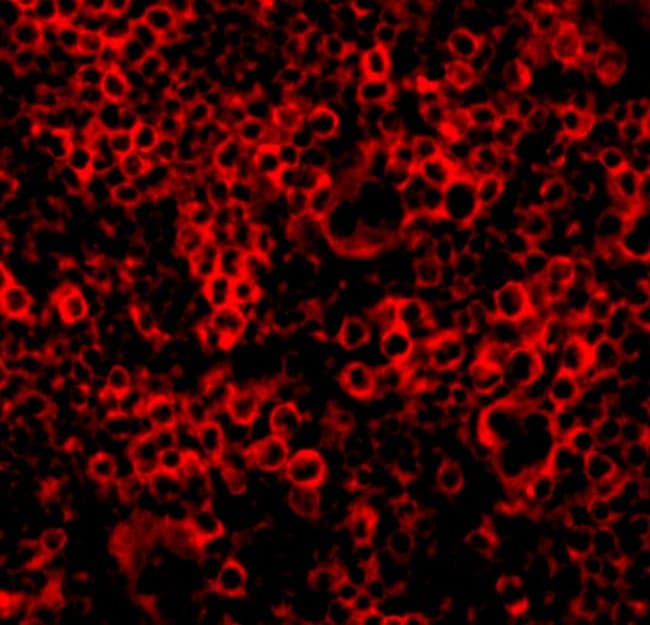

Immunohistochemistry, Western Blot, Immunocytochemistry

A suggested positive control is Ramos cell lysate. PA5-20108 can be used with blocking peptide PEP-0226.